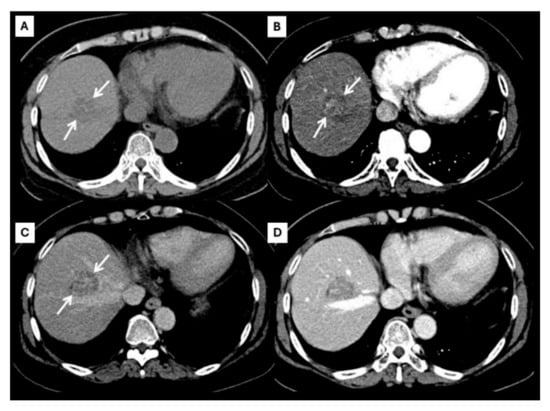

| Later arterial phase | Arterial phase hyperenhancement | Rim-like enhancement |

| Portavenous phase | Non-peripheral washout | Progressive peripheral enhancement |

| Delayed phase | Capsule enhancement | Progressive peripheral enhancement |